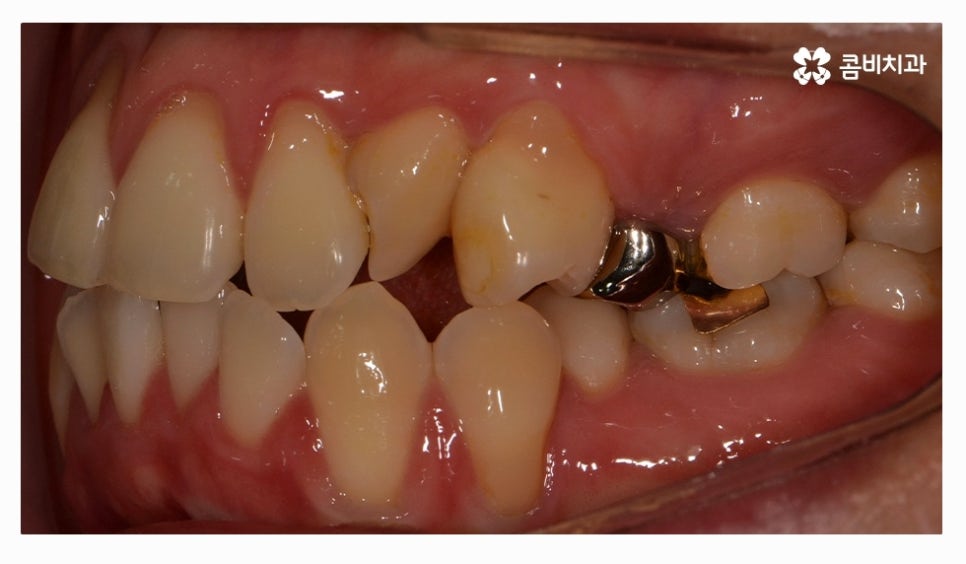

오늘 소개드릴 환자분은 윗니와 아랫니가 제대로 맞물리지 않는

부정교합 사례이며 클리피씨교정을 통해서 치료가 진행된 사례라고 할 수 있어요.

전체교정을 하시는 분들의 경우 보편적으로 많이 선택하시는

교정 장치는 클리피씨교정이라고 할 수 있을 정도로 선호도가 높으며

클리피씨교정은 자가 결찰 장치로 통증 감소 및 교정 기간을

단축시킬 수 있으며 관리가 편리하다는 장점도 갖고 있어요